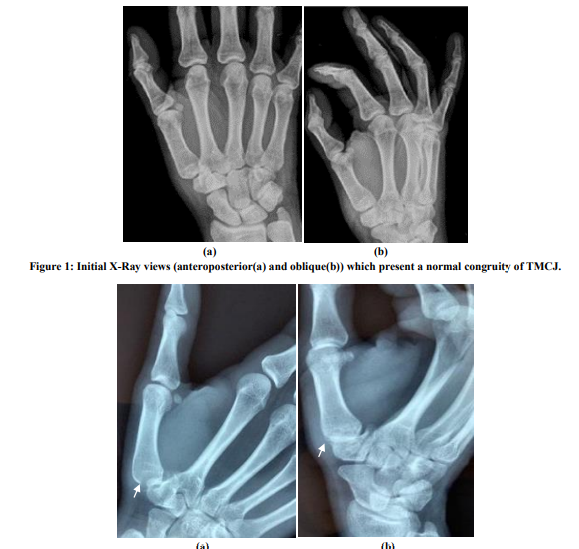

Acute Traumatic Isolated Subluxation of Trapeziometacarpal Joint: Case Report-Literature Review

Kastanis G, Pantouvaki A, Trachanatzi E, Stavrakakis I, Chaniotakis C, Siligardou M. K., Kapsetakis P.

International Journal of Innovative Research in Medical Science·October 5, 2022